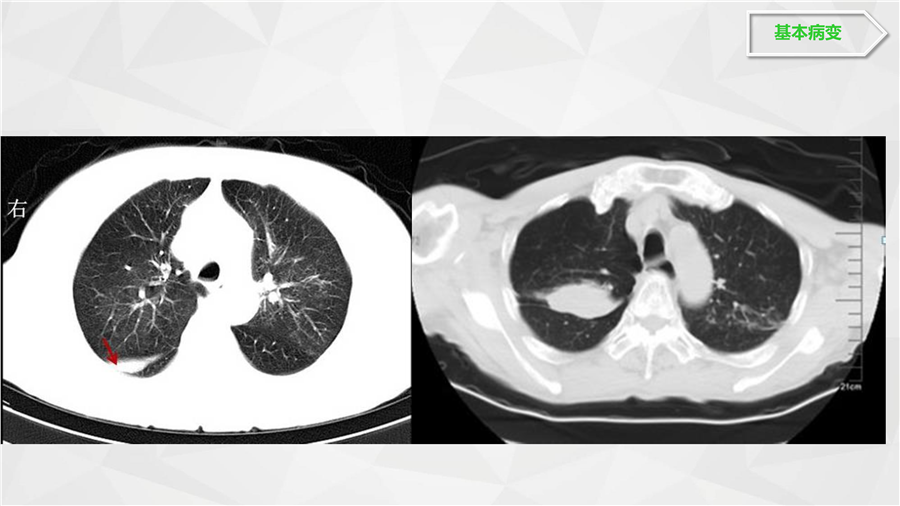

呼吸系统二